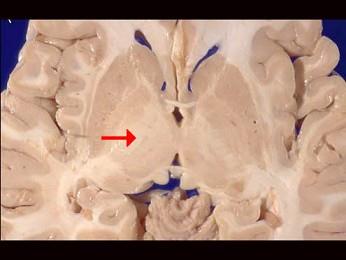

问题 如图箭头所示为大脑哪个部位 ( )

选项 A、内囊 B、齿状核 C、丘脑 D、尾状核 E、壳核 一、单项选择题

答案 A